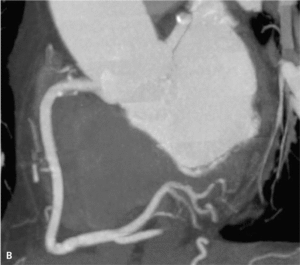

RYCINA 2. Obrazowanie widmowe z zastosowaniem różnych energii u pacjenta po wszczepieniu metalowych elementów stabilizujących kręgosłup lędźwiowy.

5. Coraz szersze stosowanie obrazowania widmowego w TK (spectral imaging) umożliwiające oddzielenie obrazów z separacją odpowiednich materiałów, z których się składają. Najczęściej dotyczy to: wody, środków cieniujących jodowych i wapnia. Może to mieć duże znaczenie w kardiologii. Obrazowanie widmowe pozwala wyeliminować artefakty od metalu (stenty, imlanty, zwapnienia, ryc. 2), zmniejszyć objętość podanego środka cieniującego (pacjenci z nefropatią) oraz umożliwia z większą dokładnością diagnozować ubytki środka cieniującego z łożyska naczyniowego (zatorowość).